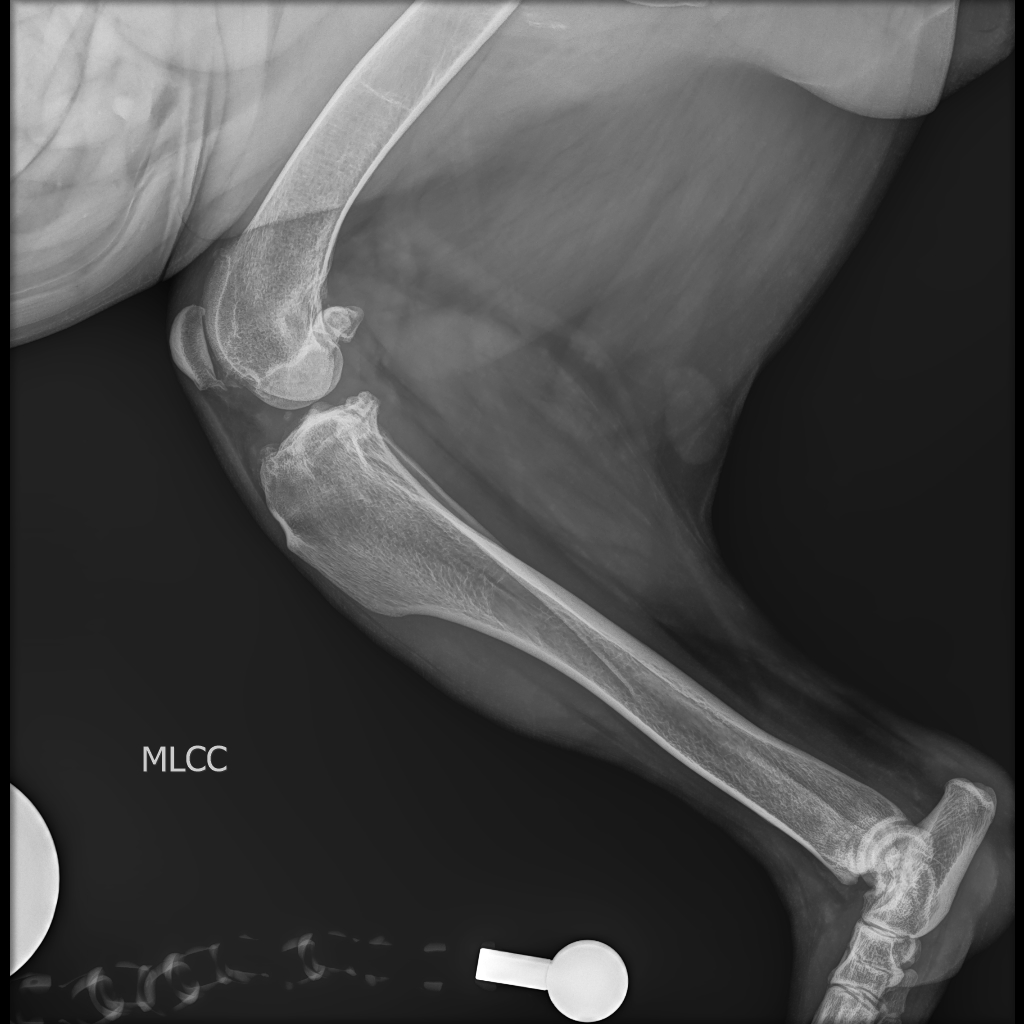

Traumatología

En Instituto Neurológico Veterinario contamos con un servicio especializado de traumatología veterinaria, enfocado en la consulta y monitoreo de pacientes hospitalizados con fracturas, luxaciones, lesiones articulares y afecciones óseas complejas. Nuestros especialistas en traumatología y ortopedia realizan diagnósticos precisos mediante radiografías y estudios avanzados, y aplican técnicas quirúrgicas modernas para una recuperación segura y funcional. Además, el servicio incluye fisioterapia y rehabilitación postoperatoria, fundamentales para optimizar la movilidad, reducir el dolor y acelerar el retorno a la actividad normal de cada paciente.